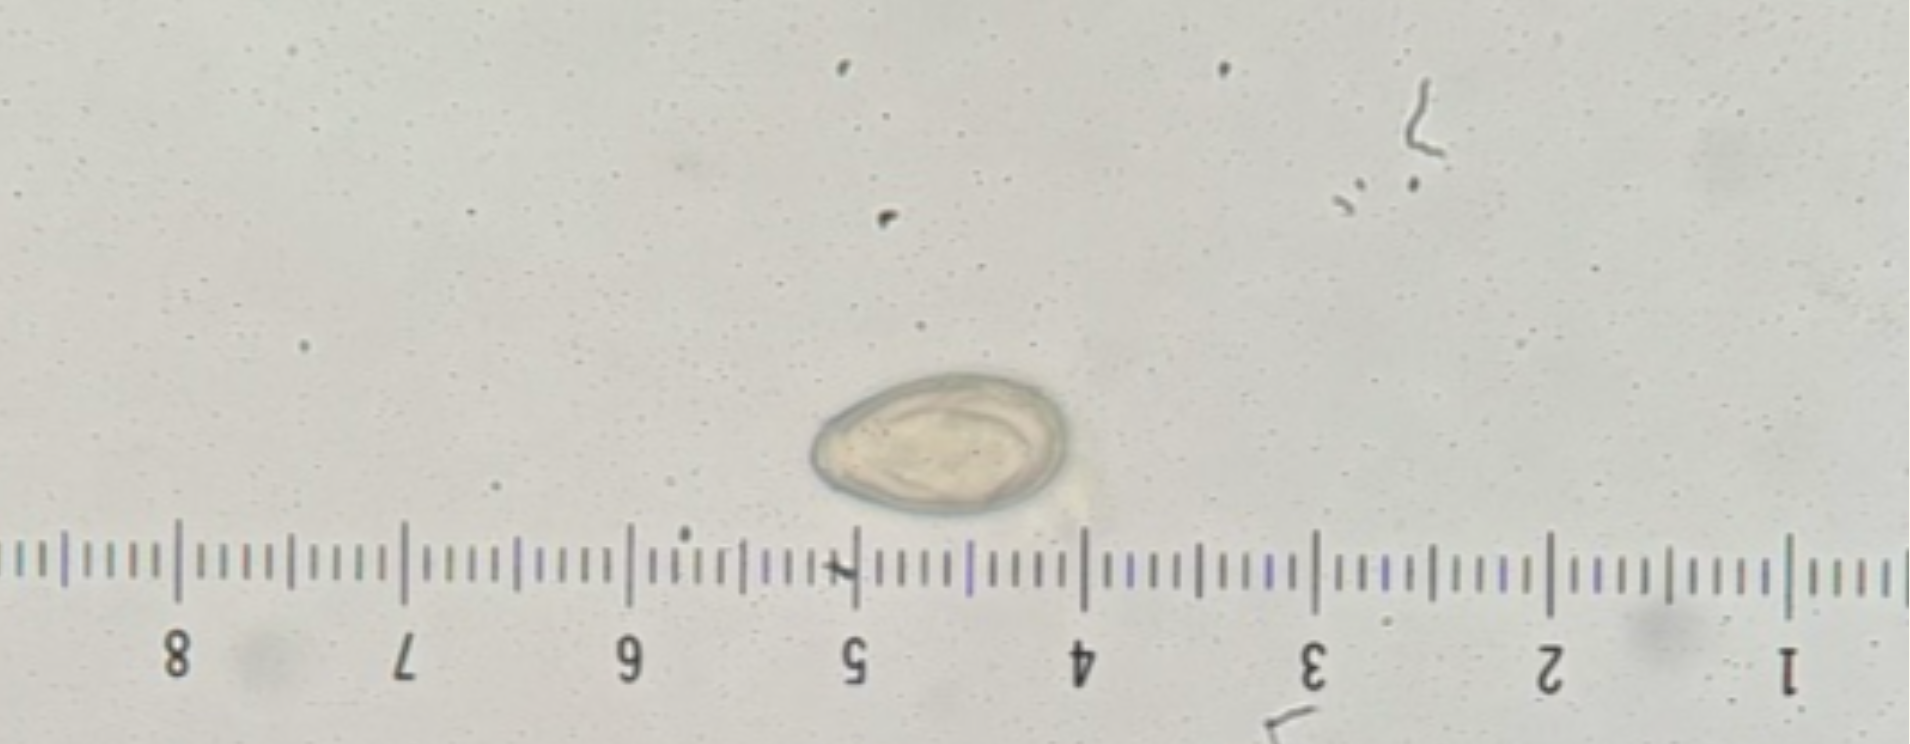

Kingdom: Animalia

Phylum: Platyhelminthes

Class: Cestoidea

Subclass: Eucestoda

Order: Cyclophyllidea

Family: Taeniidae

ID: taeniid egg